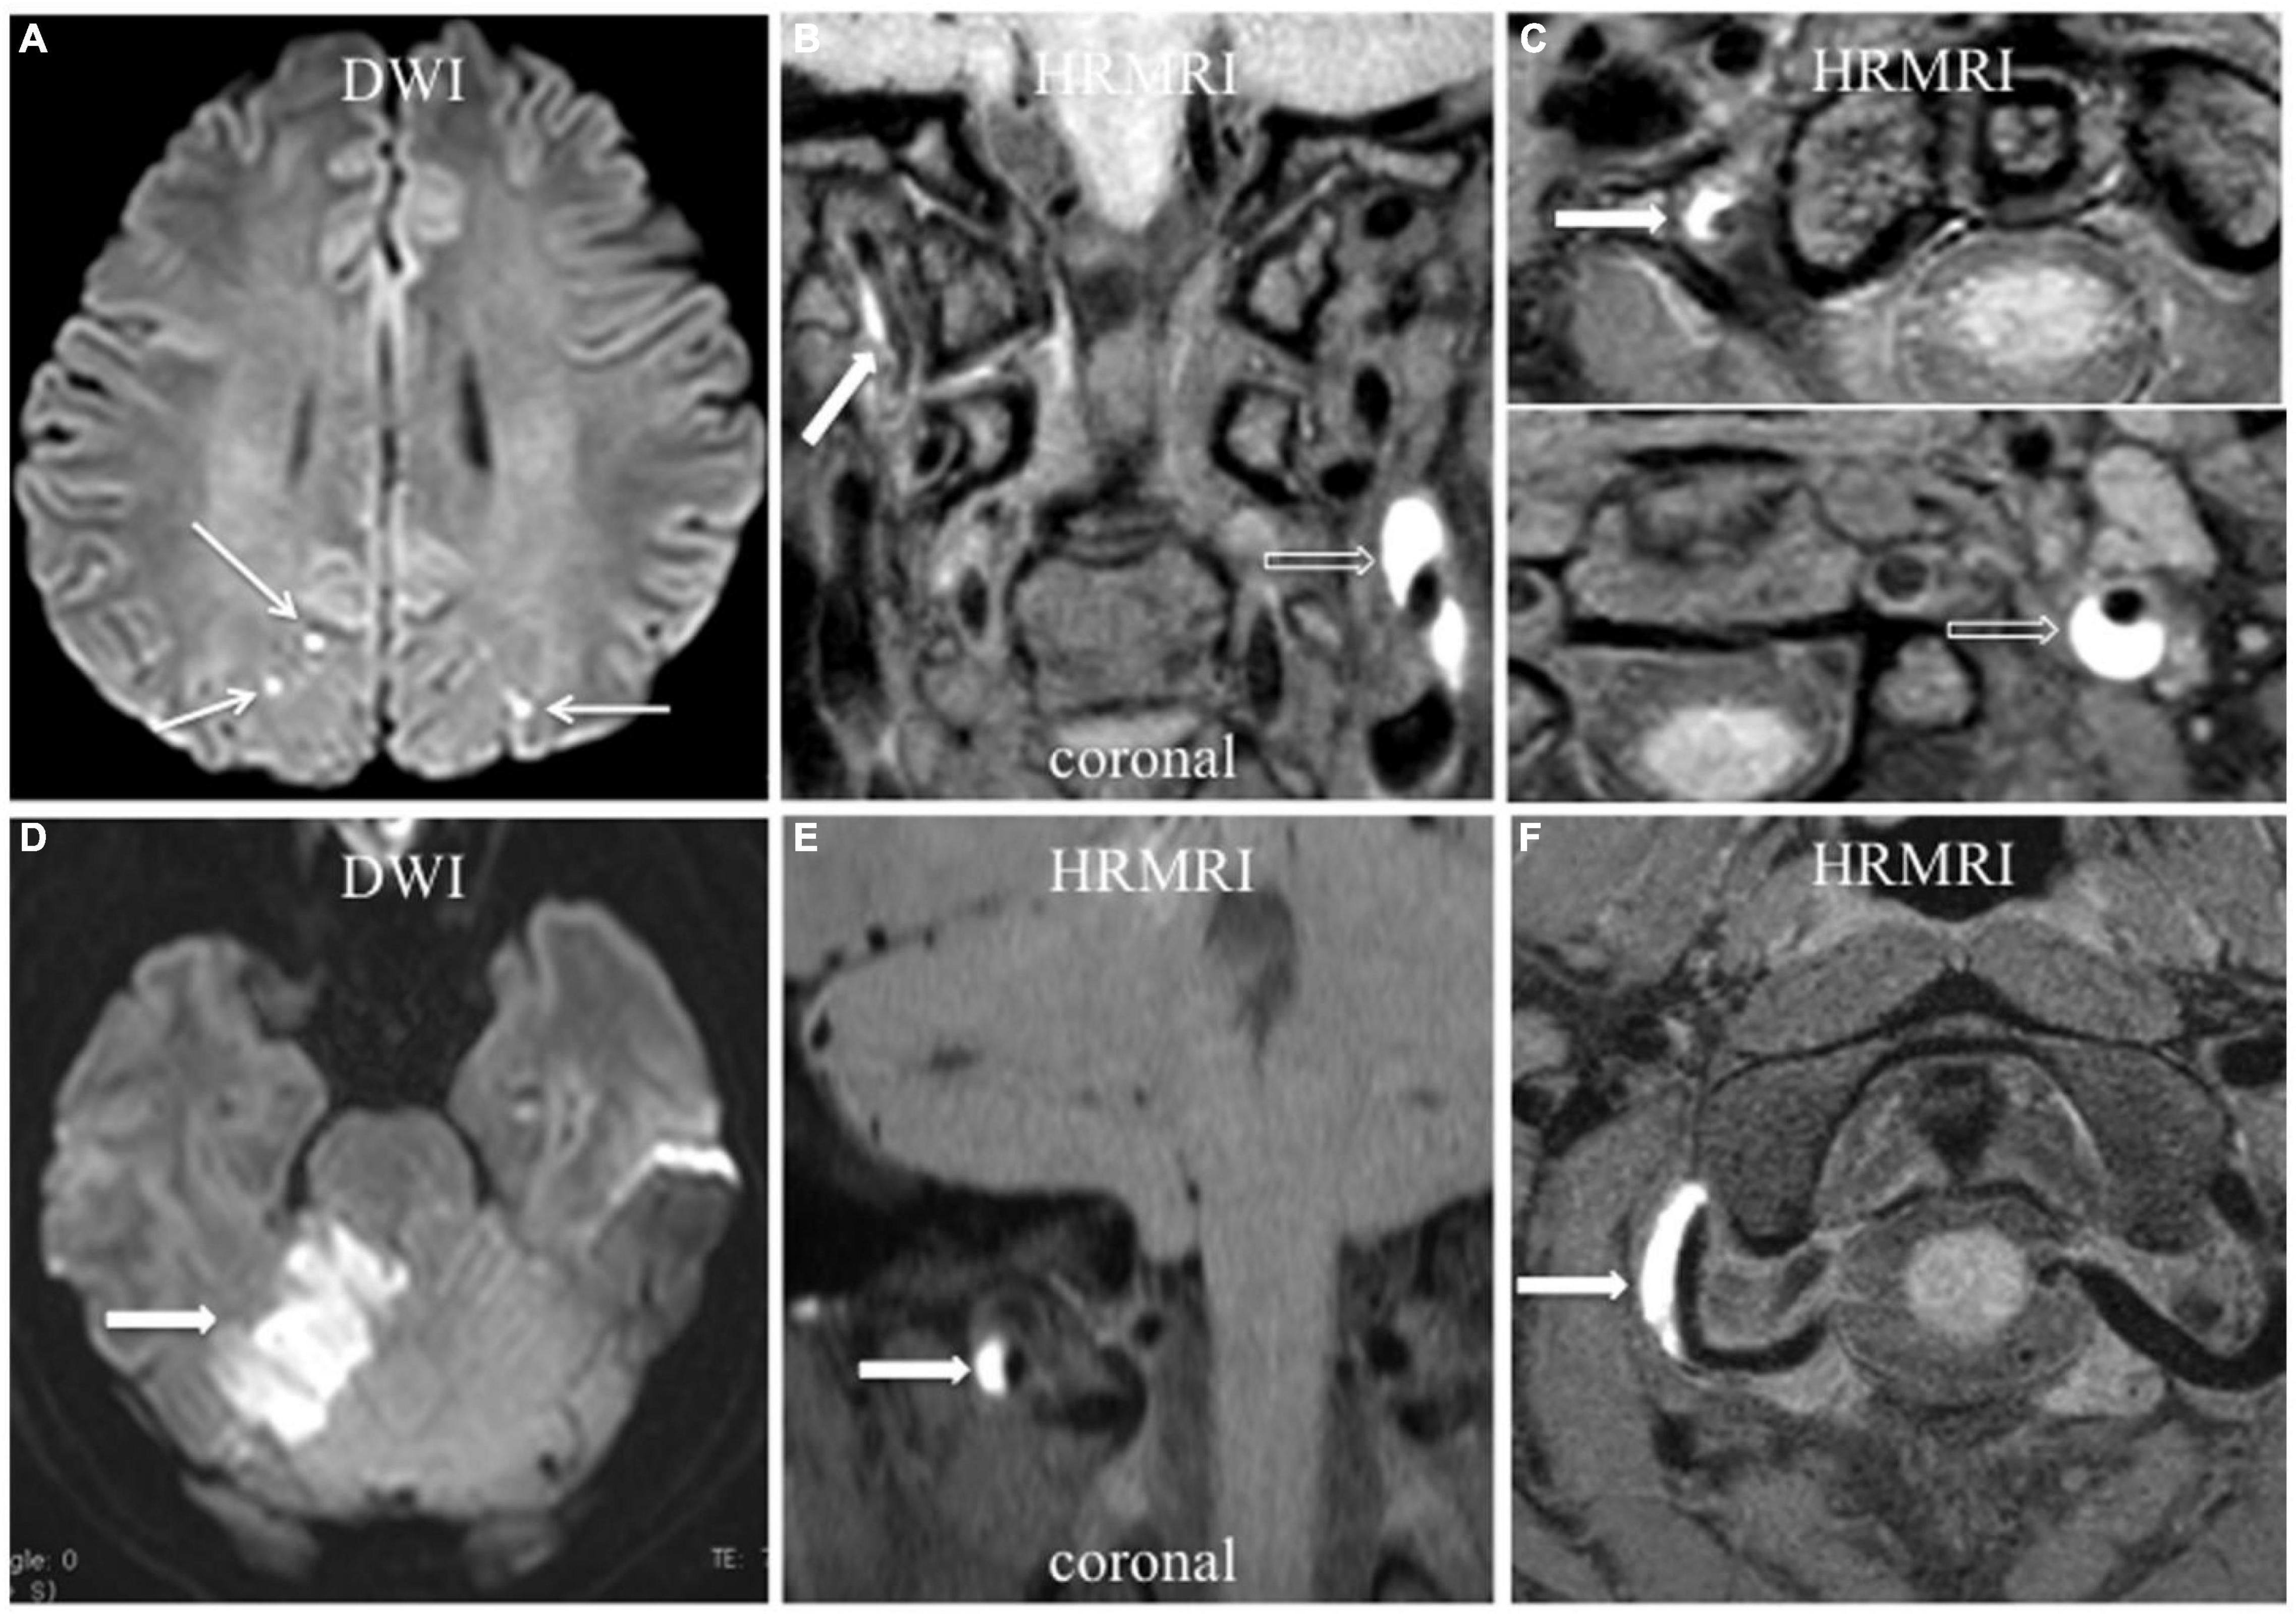

FIGURE 4

Acute ischemic stroke associated with vertebral artery dissection. (A–C) Multiple acute ischemic stroke lesions in the parietooccipital junction bilaterally (A, arrow) with dissection in the right vertebral artery and left ICA. T1-weighted HRMRI showed an intramural hematoma in the right vertebral artery (B,C, arrow) and left ICA (B,C, empty arrow) in the coronal and transverse planes. (D–F) Acute ischemic stroke in the right cerebellum (D, arrow) with V3 segment dissection of the right vertebral artery. T1-weighted HRMRI showed an intramural hematoma in the right vertebral artery in the coronal (E, arrow), and transverse (F, arrow) planes.